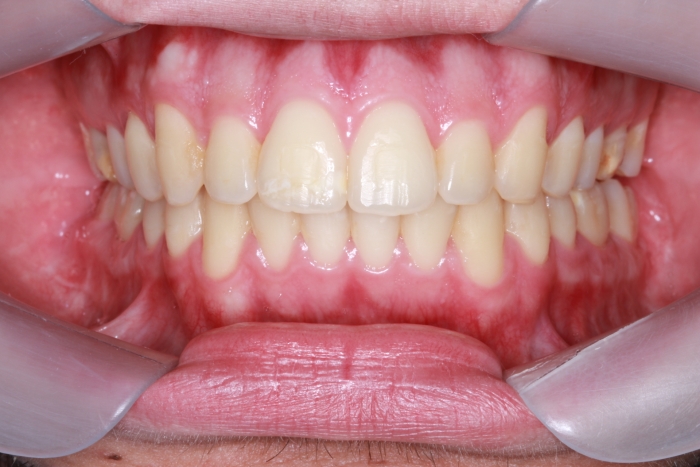

Mordida após cirurgia realizada em 2015 - Clínica Cliniface

Mordida após cirurgia realizada em 2015